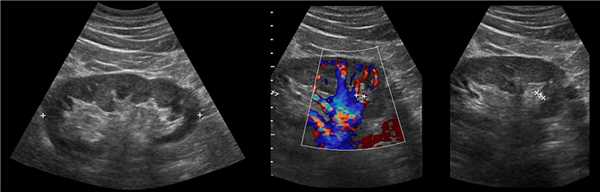

Рисунок. КТ-урография (1) показывает неполное удвоение ЧЛС слева: два мочеточника соединяются на входе в таз и единым мочеточником вступают в мочевой пузырь; внутрипузырная часть мочеточника расширена (красная стрелка) — уретероцеле. Уретероцеле хорошо видно на рентгенограммах (2) при экскреторной урографии: правый мочеточник расширен на всем протяжении, дистальный отдел кистозно расширен — «голова кобры».

Рисунок. Уретероцеле (стрелка) на УЗИ и КТ.

Рисунок. Дистальный отдел мочеточника расширен, в мочевом пузыре анэхогенное образование с тонким и ровным контуром — уретероцеле.